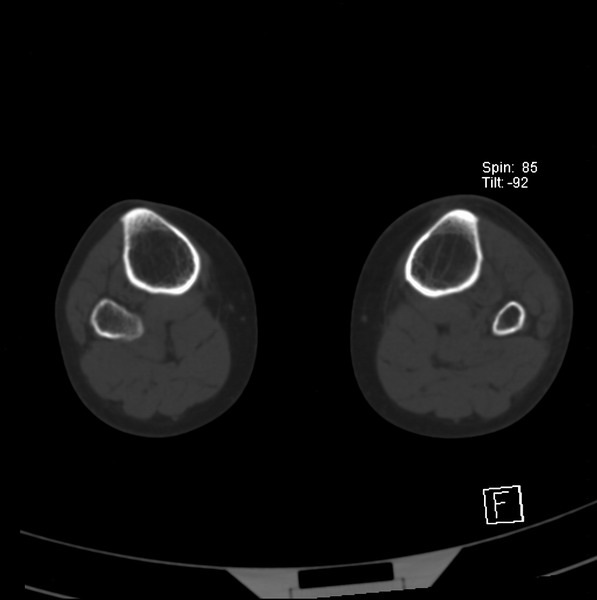

标题: CT21917:右腓骨小头是否骨软骨瘤? [打印本页]

标题: CT21917:右腓骨小头是否骨软骨瘤?

女、43.

不是骨软骨瘤,“牵拽征”,正常变异。有平片吗?

正常变异,“牵拽征”,比目鱼肌牵拽.

比目鱼肌附着点